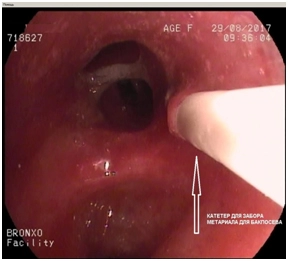

Протокол эндоскопического исследования (от 29.08.2017 г.).

Заключение: патологических изменений трахеобронхиального дерева, доступных диаметру аппарата, на момент осмотра не выявлено.

Щеточная биопсия из левого верхнедолевого бронха. В исследованном материале на фоне эритроцитов, множества разрушенных клеточных элементов и большого количества полисегментоядерных гранулоцитов и альвеолярных макрофагов обнаружены отдельно расположенные и в небольших скоплениях цилиндрические клетки бронхиального эпителия с признаками пролиферации и выраженными реактивными изменениями; отмечается плоскоклеточная метаплазия. Цитограмма выраженного неспецифического воспаления.